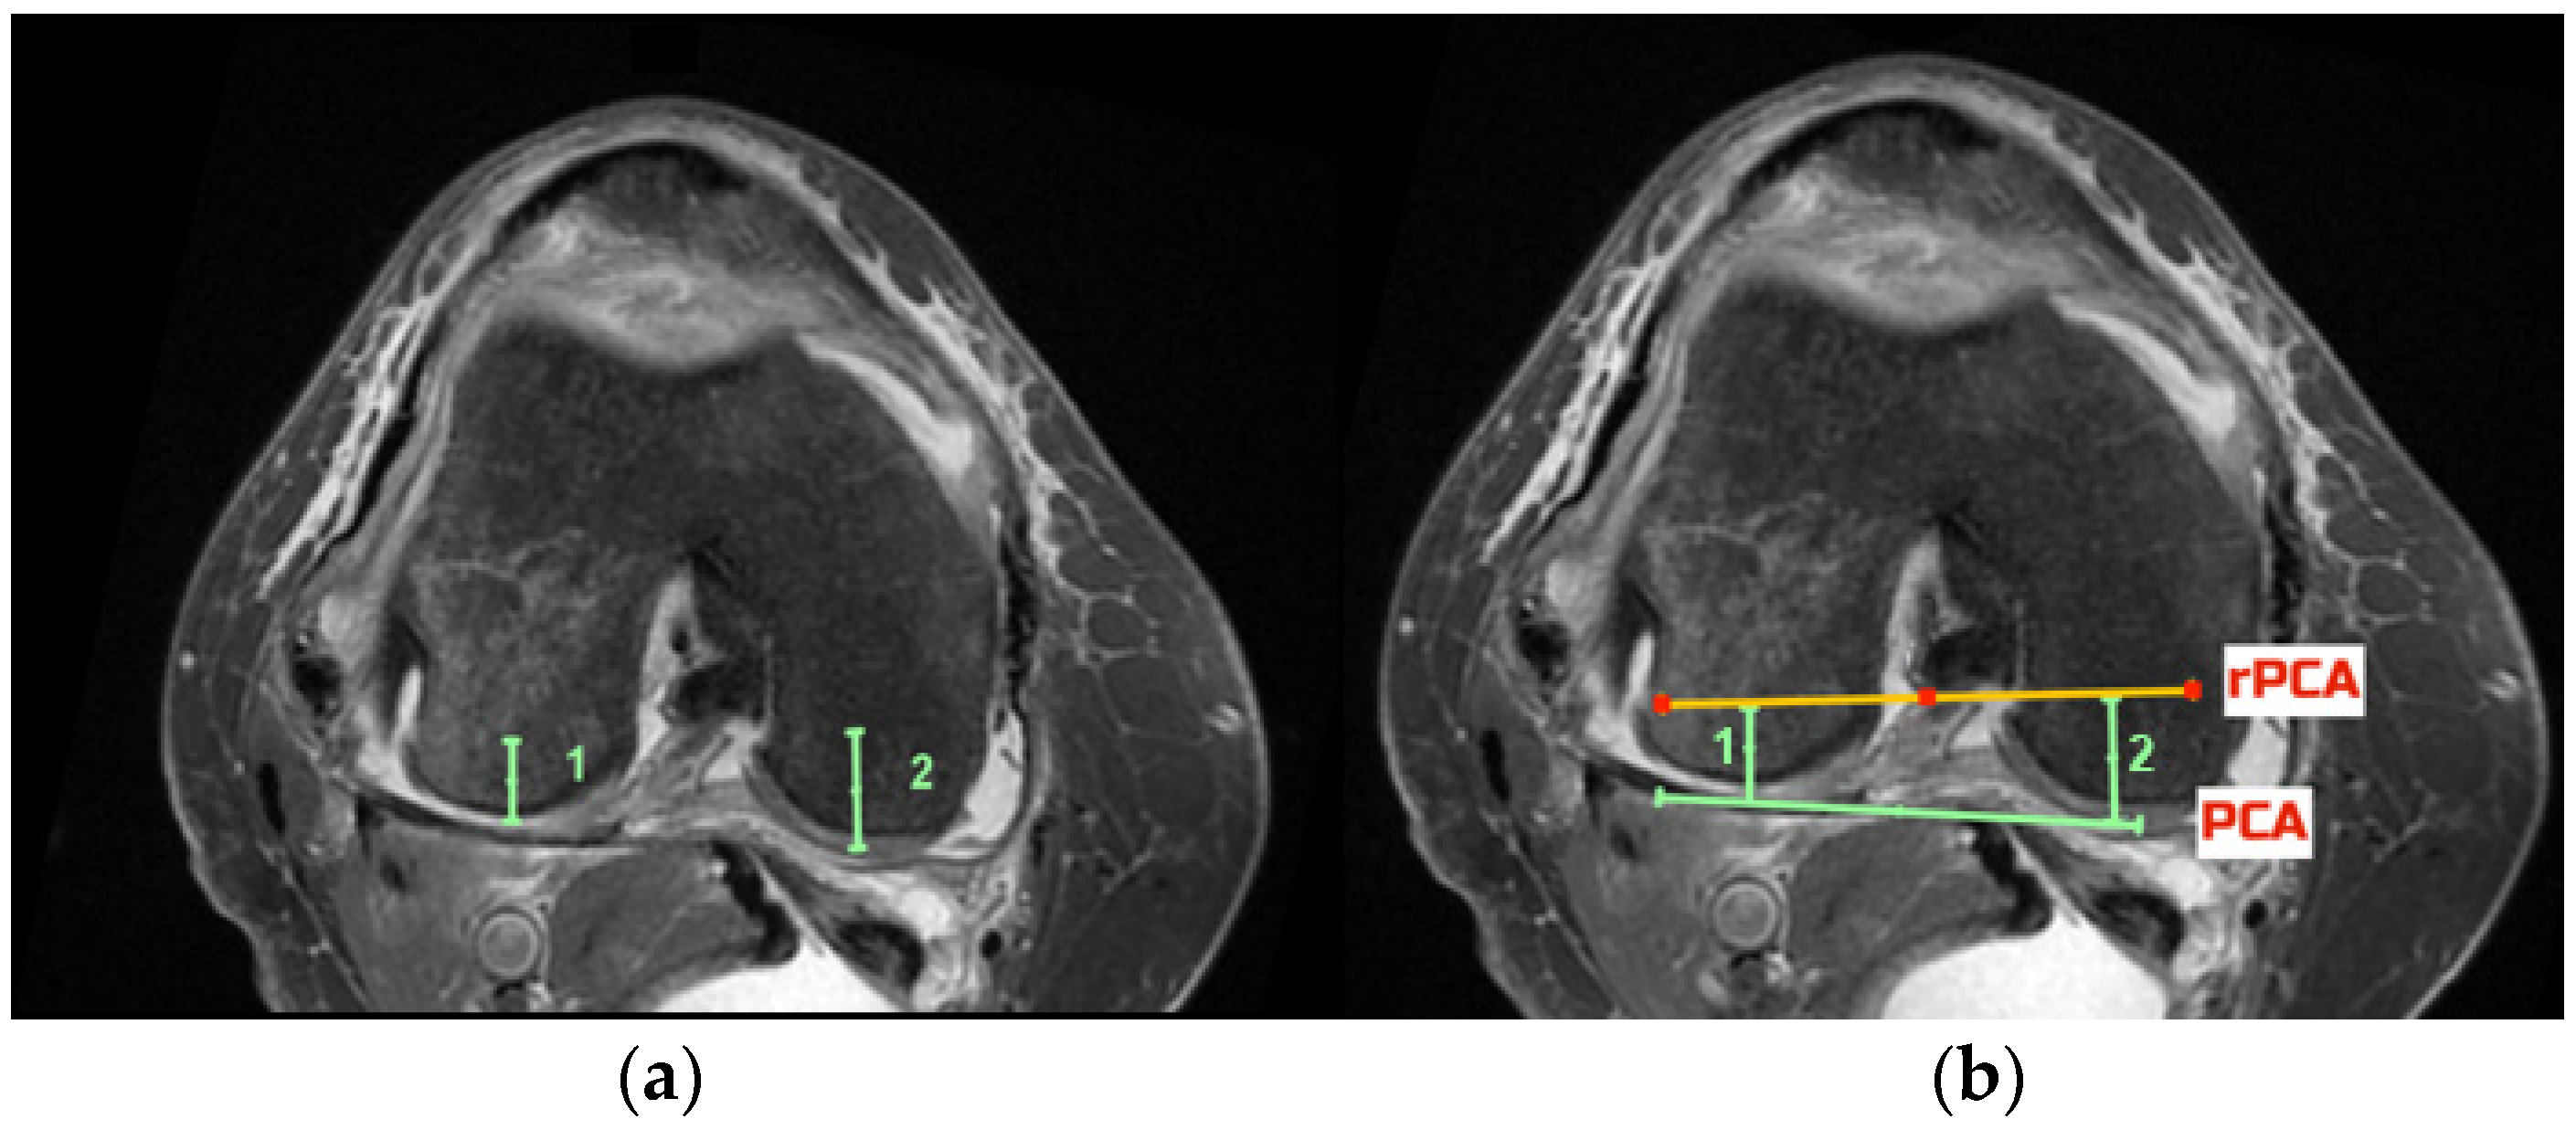

2.5. Radiological Outcomes